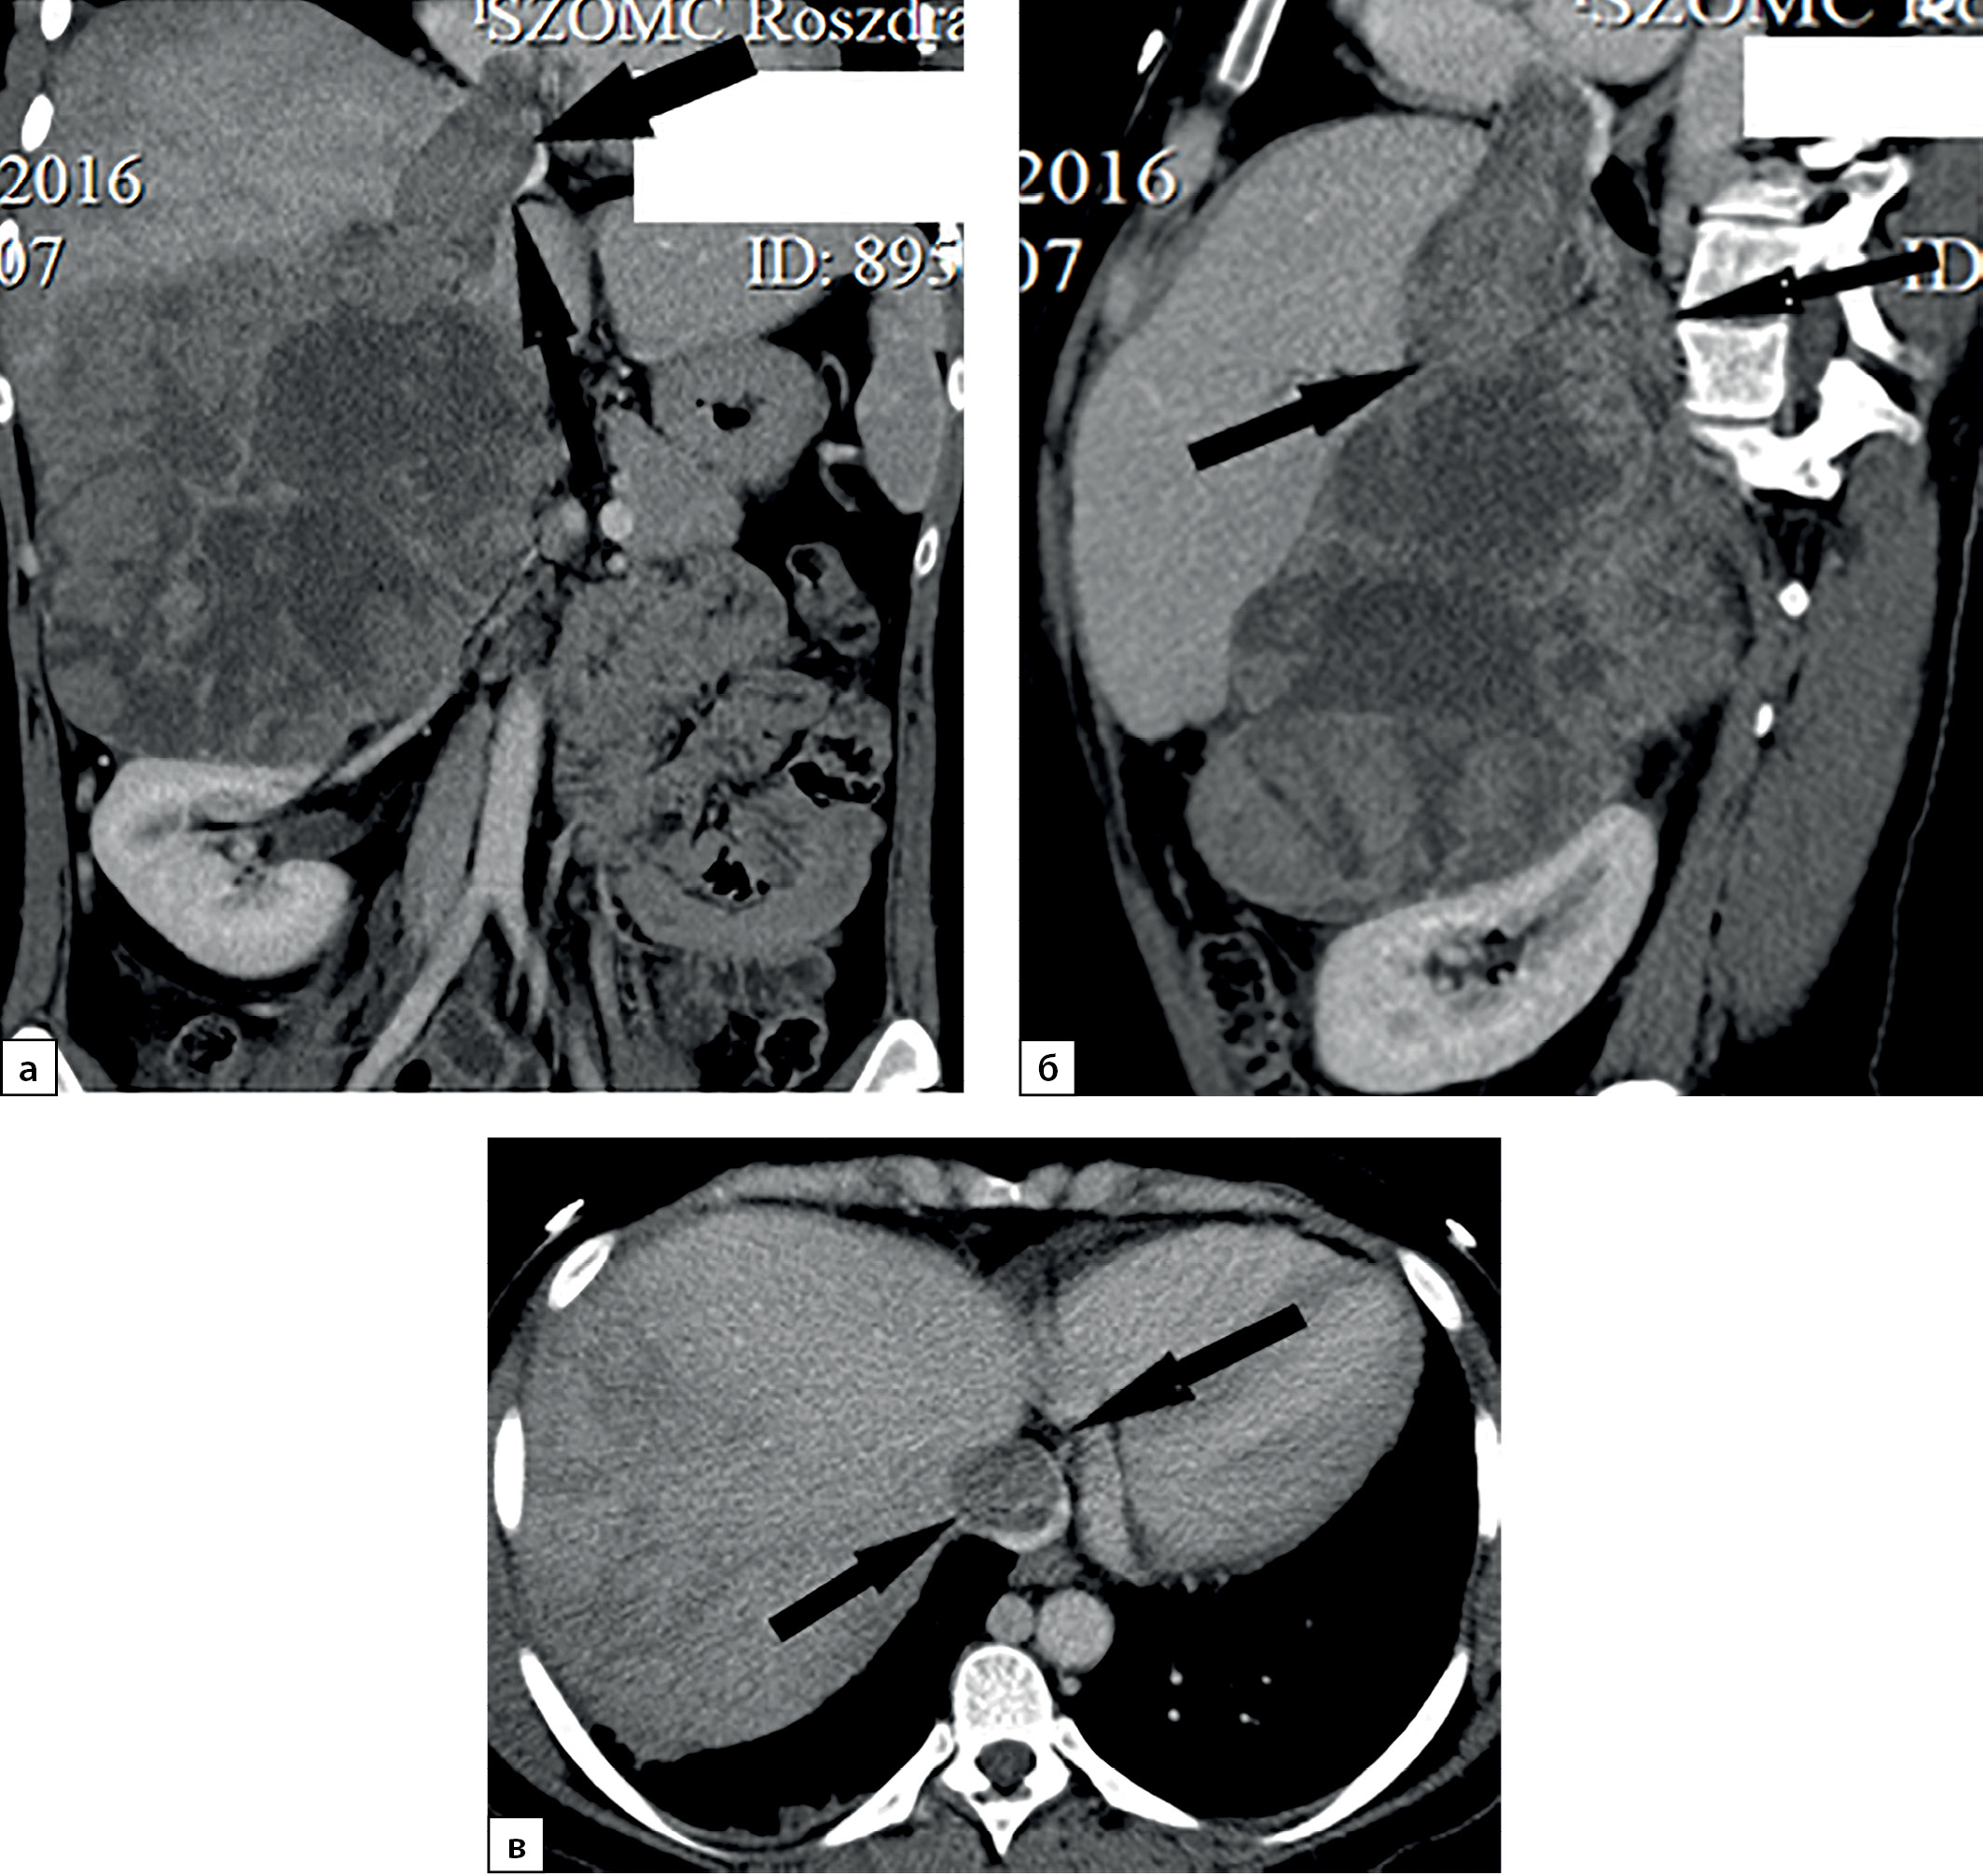

Рисунок 2. Компьютерные томограммы пациентки В., 70 лет с гигантской опухолью левого надпочечника (137х80 мм), деформирующая тело и хвост поджелудочной железы: а — изображение реформатированное в корональной плоскости, нативная фаза сканирования, в структуре мягкотканного образования с денситометрическими показателями до 28HU включения с низкой плотностью (до -59HU), соответствующие жировой ткани; б — артериальная фаза, включения жира не накапливают контрастный препарат.

Figure 2. Computed tomography of patient V., 70 years old, with a giant tumor of the left adrenal gland (137x80 mm), deforming the body and tail of the pancreas: a — image reformatted in the coronal plane, native scanning phase, in the structure of the soft tissue formation with densitometric parameters up to 28HU inclusion with low density (up to -59HU), corresponding to adipose tissue; b — arterial phase, inclusions of fat do not accumulate a contrast agent.